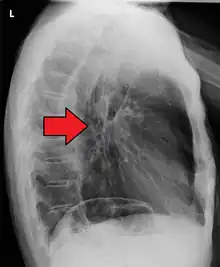

If the cancer has spread elsewhere, symptoms related to metastatic disease may appear. Common sites of spread include nearby lymph nodes, the liver, lungs and bone.[14] Liver metastasis can cause jaundice and abdominal swelling (ascites). Lung metastasis can cause, among other symptoms, impaired breathing due to excess fluid around the lungs (pleural effusion), and dyspnea (the feelings often associated with impaired breathing).